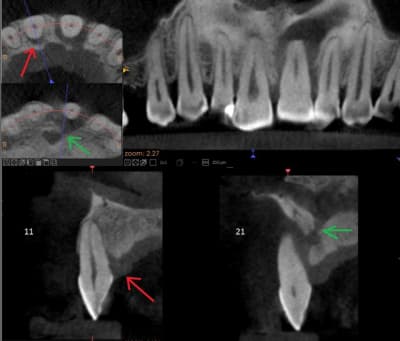

Patient adressé par une consœur pour sa 21. Fume un paquet.

1 : Pensez vous que la cause de la lésion soit occlusale, justement ( cela aurait pu débuter comme sur la 11, flèche rouge ) ?

2 : quid de la jonction avec le canal nasopalatin ( flèche verte ) ?

Sinon la question peut sembler idiote mais la 21 est vitale ou non vitale ? je demande car d'après la radio je n'ais pas l'impression que se soit une lésion endo et il n'y a pas de changement de teinte par rapport a la 11.

L'apex est atypique au scann, je pense qu'il n'y a plus de vascularisation ici.

Et a part la supra, la jonction avec le canal naso palatin ne gene personne pour la reconstruction osseuse ?